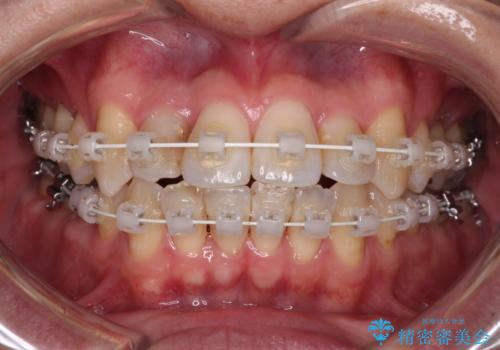

- 矯正装置

- 審美装置

- 治療期間

- 2年2ヶ月